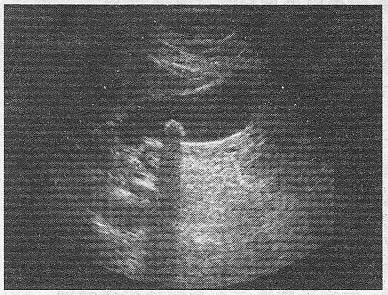

3.如图,胆囊结石与胆囊息肉超声最主要鉴别点是

A.是否有声影

B.回声强度

C.是否随体位改变而移动

D.是否有血流

E.体积大小

正确答案:AC 解题思路:胆囊结石声像图显示①强光团;②后伴声影;③可移动。胆囊息肉声像图显示:①强光团;②无声影;③不移动。